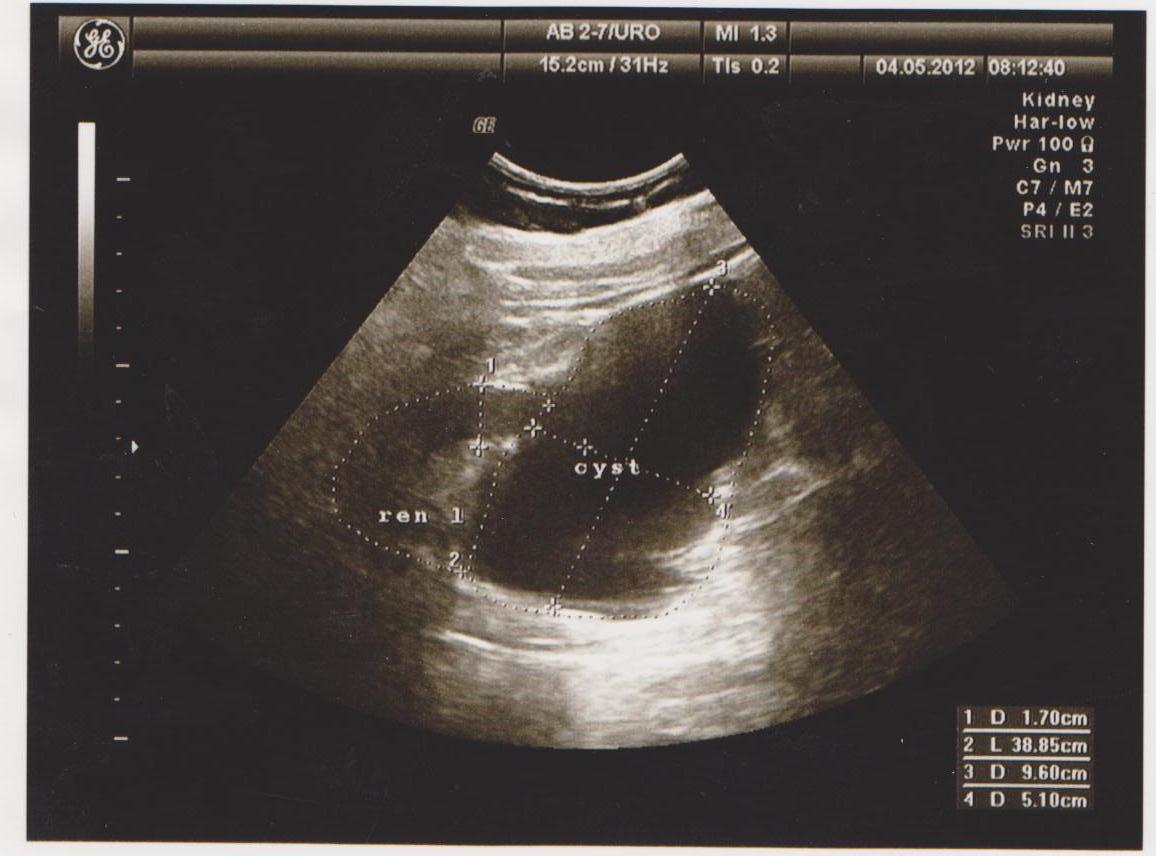

Частые болезни: кисты, новообразования (ангиомиолипомы, гемангиомы, фибромы…), конкременты (камни), расширение мочевых путей (расширение лоханки или чашечек — пиелоэктазия, гидронефроз), хроническое воспаление (пиелонефрит), смещение почек (опущение — нефроптоз, нахождение в нетипичном месте — дистопии), удвоение почки, рак почки…

Ниже я привел пару УЗИ снимков из практики, все они есть в галерее УЗИ на сайте, смотрите и не пугайтесь: